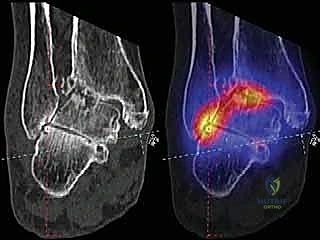

* الأشعة المقطعية (CT Scan): للحصول على رؤية ثلاثية الأبعاد للعظام، تقييم حجم التكيسات العظمية (إن وجدت)، والتخطيط الدقيق لحجم المكونات المعدنية.

* تقييم التوازن: التأكد من عدم وجود تشوهات في القدم (مثل القدم المسطحة الشديدة أو التقوس) التي قد تؤثر على عمر المفصل الصناعي. إذا وجدت هذه التشوهات، قد يقرر الدكتور هطيف إصلاحها جراحياً في نفس الوقت لضمان بيئة ميكانيكية مثالية للمفصل الجديد.